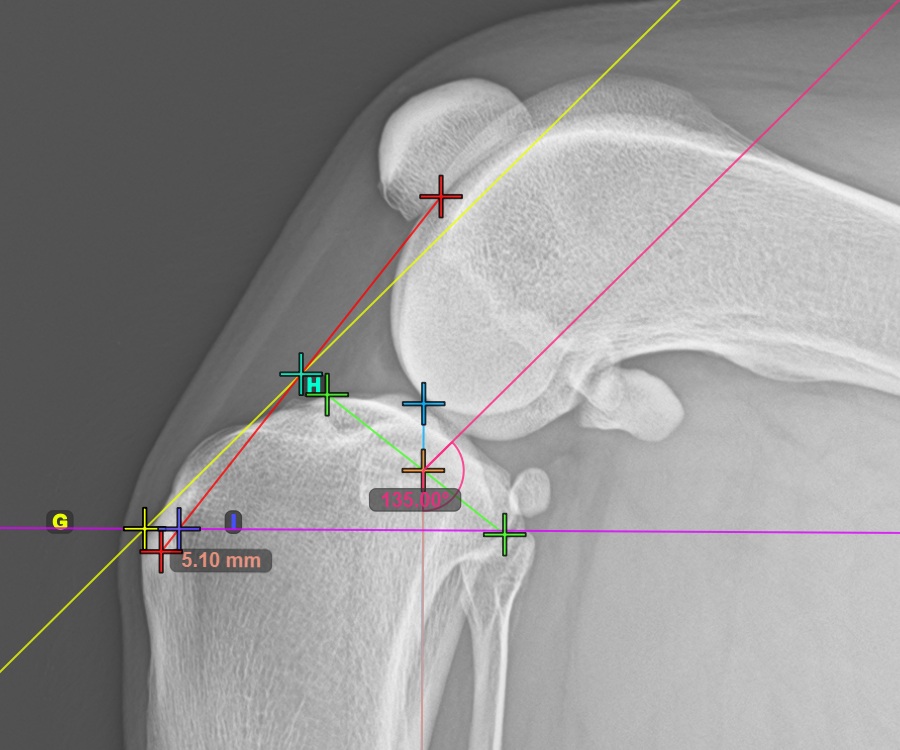

Mark the most caudal point of the tibial head to continue the measurement. Additionally, the software automatically draws a fixed angle measurement of 135°, with the intersection between the long axis of the tibia and the line connecting the most cranial and most caudal point acting as the vertex point for the angle.

The image below depicts the usual placement of the most caudal point on the tibial plateau.

../../_images/image390.jpg